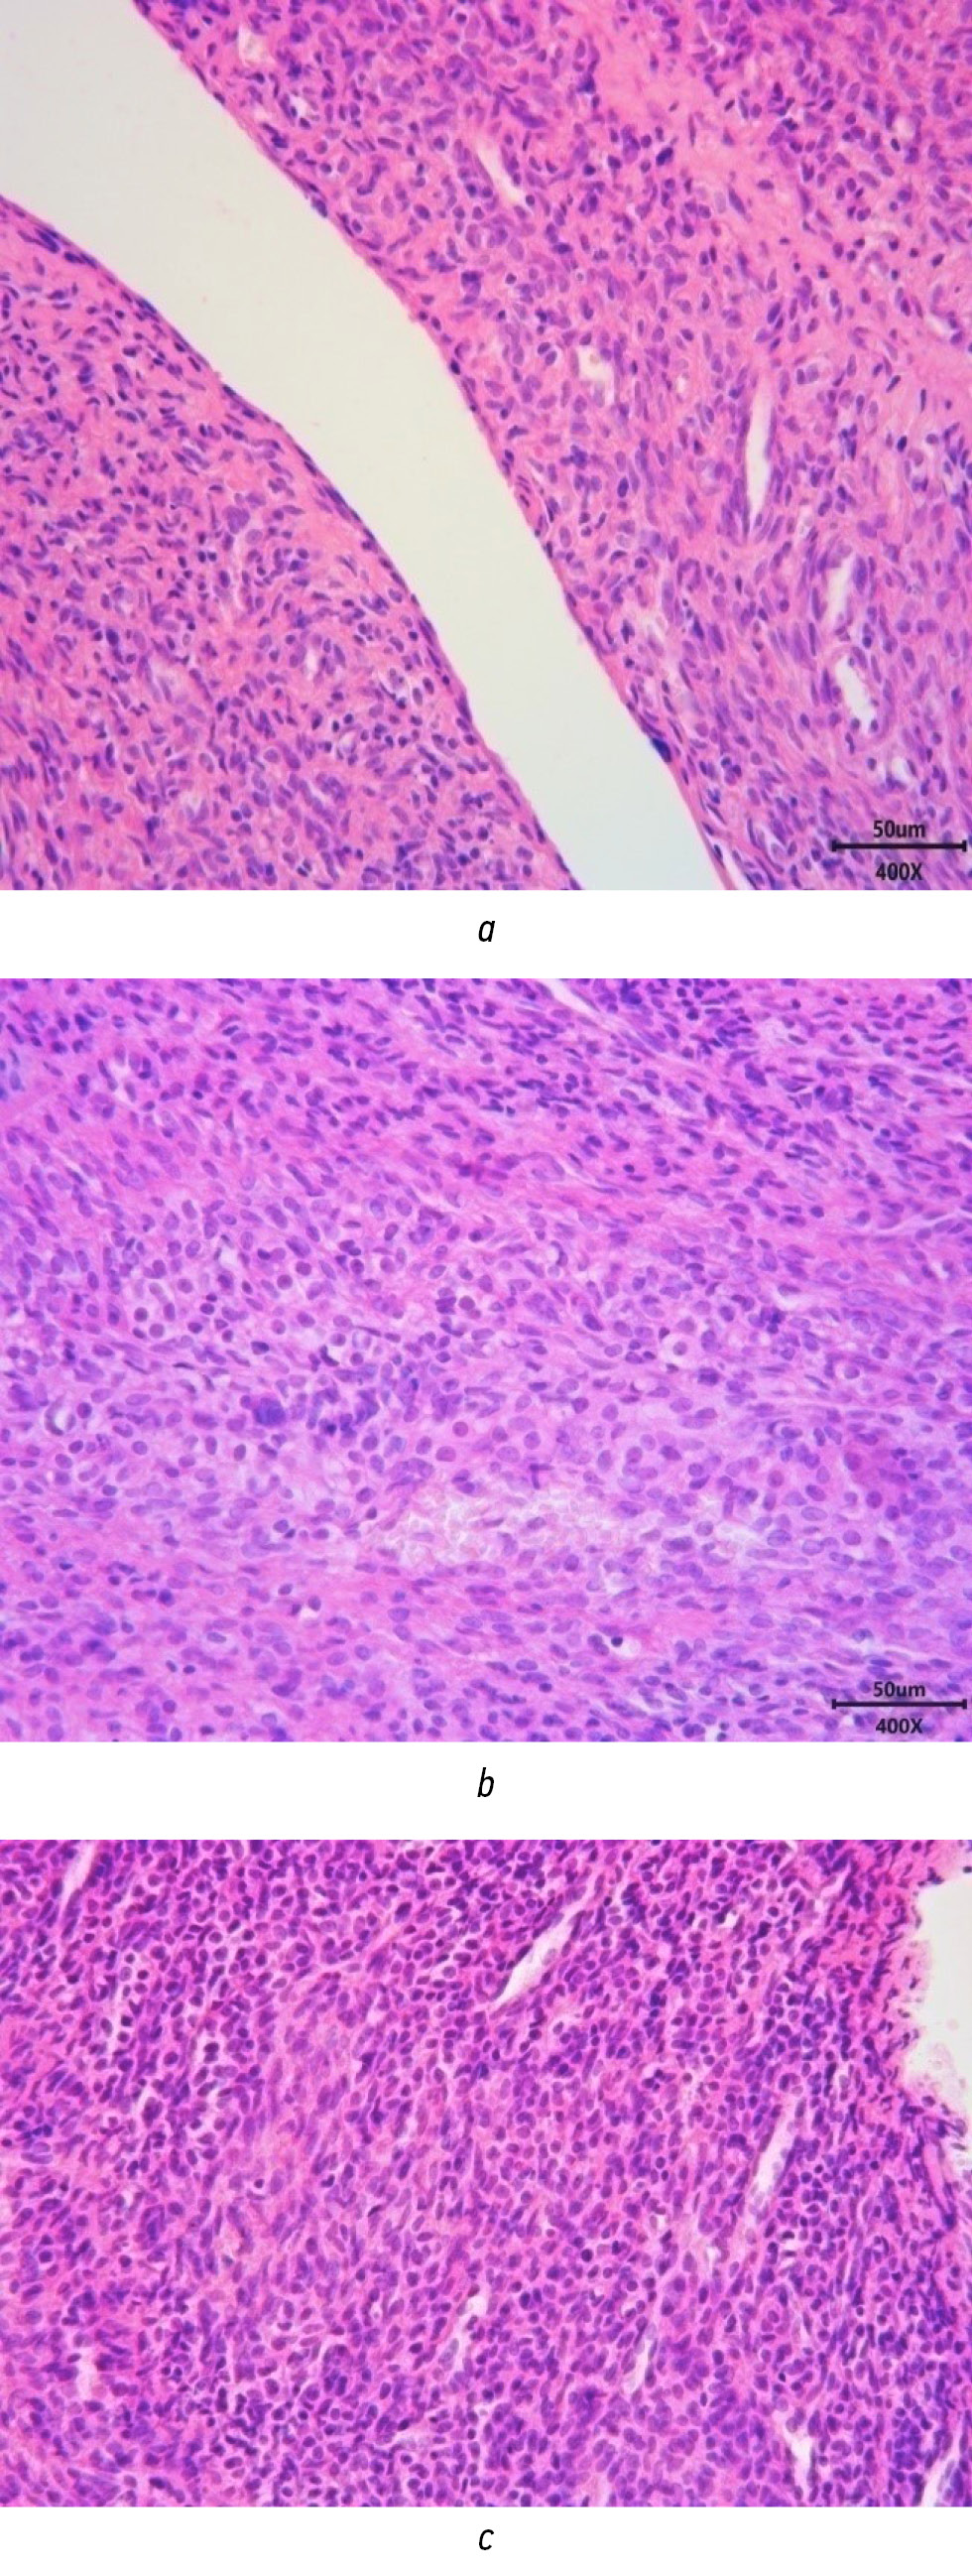

Figures 1–5 present histological images of slides from patients with PCOS-like conditions.

Fig. 1. Microscopic examination of an ovarian biopsy: a ― cyst without epithelial lining; b ― yellow body with hemorrhage; c ― pronounced hypercellularity and stroma hyperplasia.